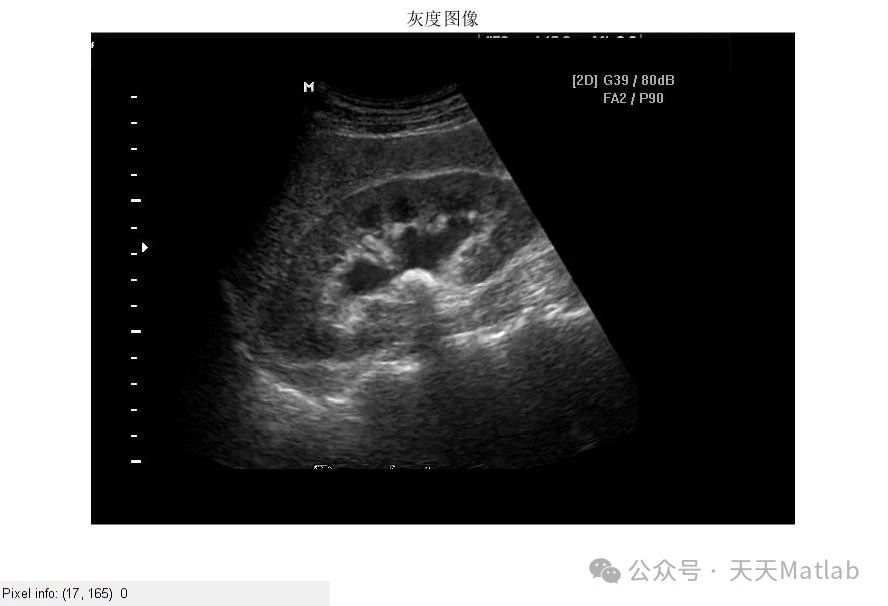

⛳️ 运行结果